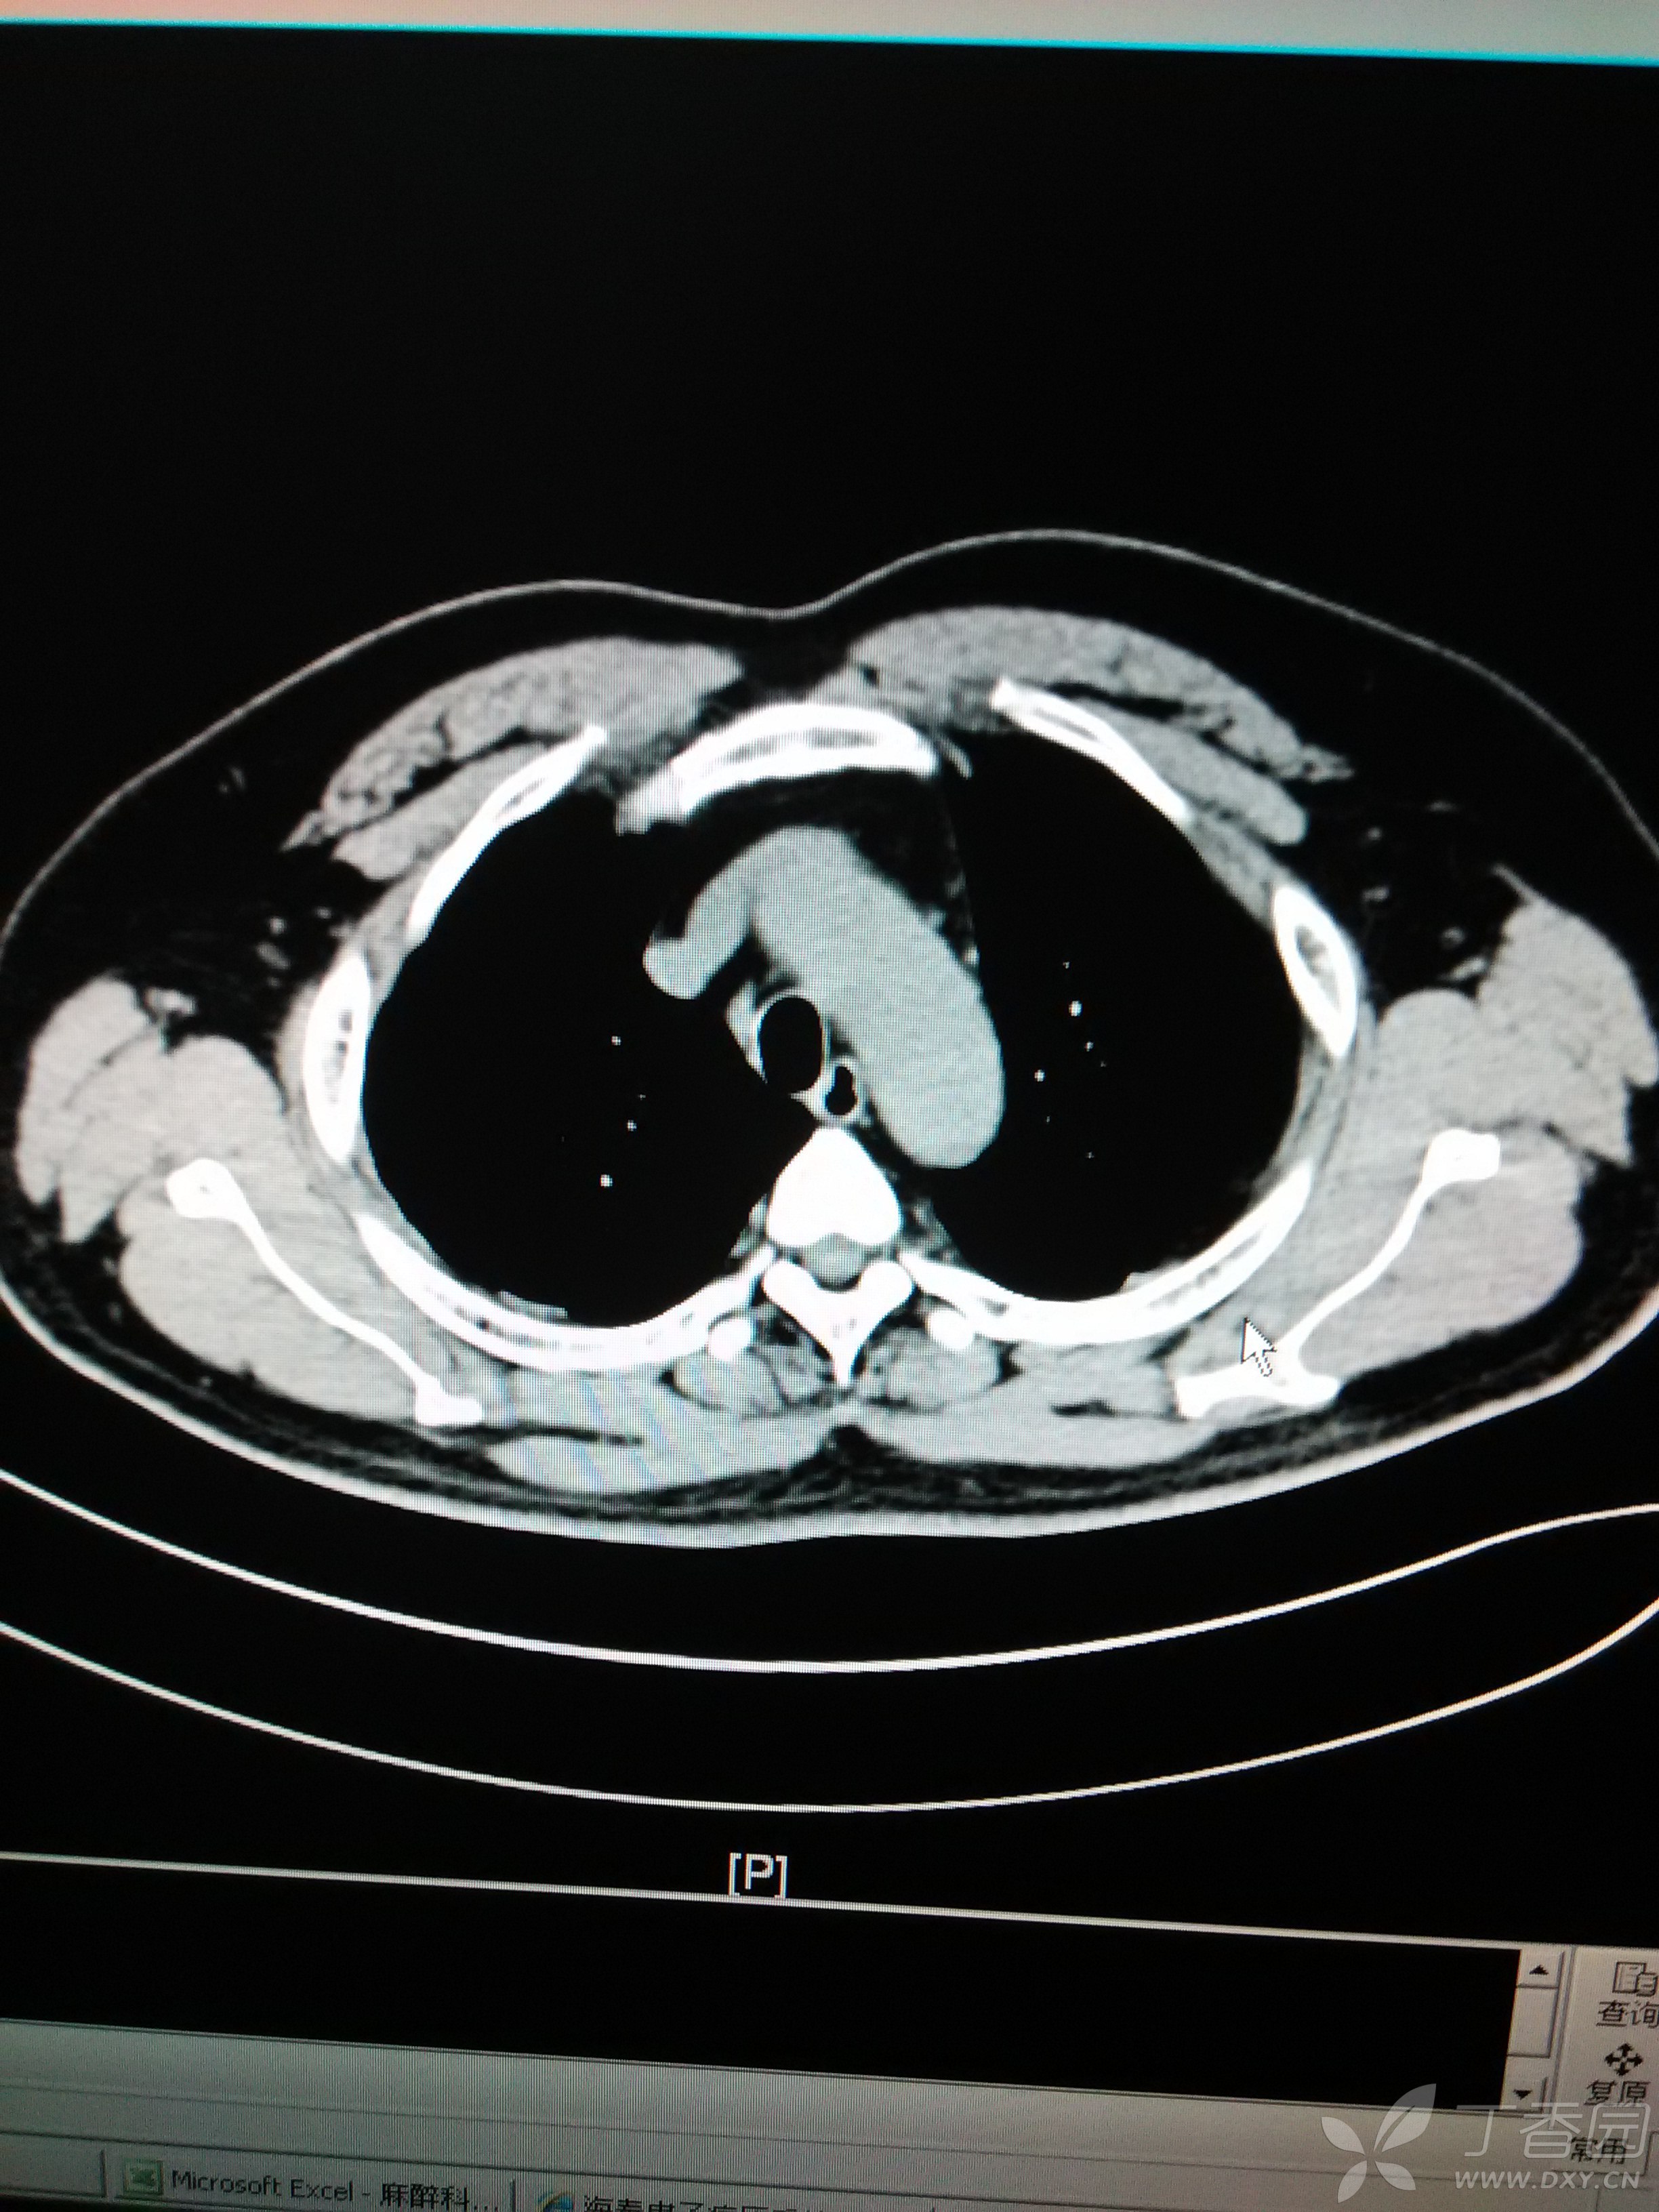

一些软组织结节,除了原发和复发的胸壁肿瘤外,最常见的就是胸壁脂肪瘤

胸腔里冒出这么大个肿物!(1 楼公布病理结果) [病例帖]